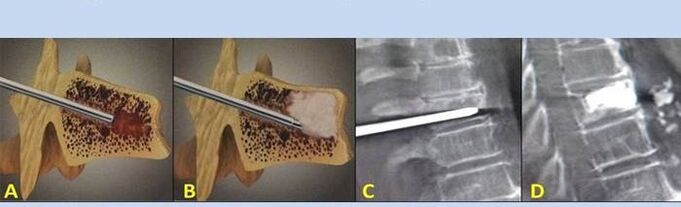

- Nucleoplasty– ablation of the nucleus of the intervertebral disc.The operation relieves pressure on the nerve endings.

- Puncture vertebroplasty– method of stabilizing the vertebrae.During the procedure, the doctor fills the cavities in the spine with bone cement.